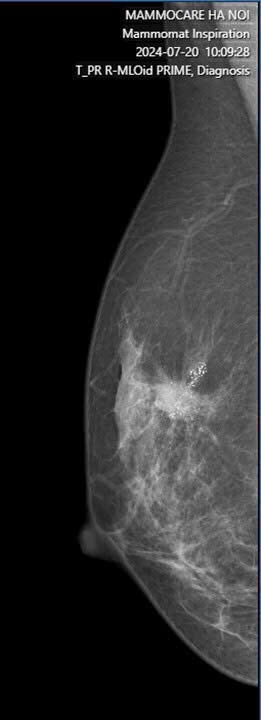

Cụ thể, kết quả X-quang cho thấy vú phải của chị có một khối nhân giảm âm với bờ tua gai trục dọc, bên trong có vôi hóa nhỏ với kích thước khoảng 12x13mm, cùng với một hạch nách phải có kích thước khoảng 13x16mm. Do kết quả nghi ngờ, chị P đã được chỉ định làm sinh thiết kim lõi và kết quả chẩn đoán là ung thư biểu mô xâm nhập, NOS, độ II, và di căn hạch nách.

Đáng chú ý, 6 tháng trước, khi chị P tiến hành đặt túi ngực, chỉ có siêu âm được thực hiện để kiểm tra. Tổn thương vi vôi hóa chỉ được phát hiện khi thực hiện chụp X-quang vú. Mặc dù tình trạng túi ngực không có gì bất thường, nhưng phát hiện ung thư vú khi được chụp X-quang đã khiến việc điều trị trở nên cần thiết và cấp bách. Hiện tại, chị P đã nhập viện K để bắt đầu điều trị ung thư.

Điều đáng nói là, khi chị P thực hiện phẫu thuật đặt túi ngực cách đây 6 tháng, chỉ có siêu âm được thực hiện để kiểm tra. Tuy nhiên, tổn thương vi vôi hóa chỉ được phát hiện khi thực hiện chụp X-quang vú. Tổn thương ung thư vú không thể được phát hiện chỉ qua siêu âm mà cần phải kết hợp với các phương pháp chẩn đoán hình ảnh khác, như X-quang vú.